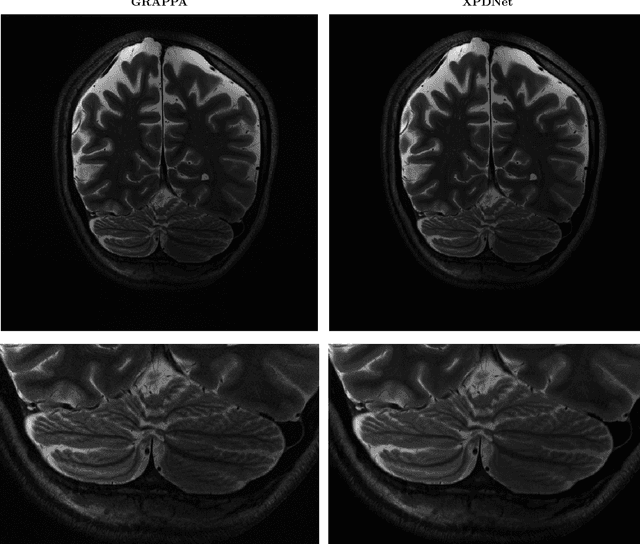

Abstract:We perform a qualitative analysis of performance of XPDNet, a state-of-the-art deep learning approach for MRI reconstruction, compared to GRAPPA, a classical approach. We do this in multiple settings, in particular testing the robustness of the XPDNet to unseen settings, and show that the XPDNet can to some degree generalize well.

Abstract:Deep neural networks have recently been thoroughly investigated as a powerful tool for MRI reconstruction. There is a lack of research, however, regarding their use for a specific setting of MRI, namely non-Cartesian acquisitions. In this work, we introduce a novel kind of deep neural networks to tackle this problem, namely density compensated unrolled neural networks, which rely on Density Compensation to correct the uneven weighting of the k-space. We assess their efficiency on the publicly available fastMRI dataset, and perform a small ablation study. Our results show that the density-compensated unrolled neural networks outperform the different baselines, and that all parts of the design are needed. We also open source our code, in particular a Non-Uniform Fast Fourier transform for TensorFlow.

Abstract:We present a modular cross-domain neural network the XPDNet and its application to the MRI reconstruction task. This approach consists in unrolling the PDHG algorithm as well as learning the acceleration scheme between steps. We also adopt state-of-the-art techniques specific to Deep Learning for MRI reconstruction. At the time of writing, this approach is the best performer in PSNR on the fastMRI leaderboards for both knee and brain at acceleration factor 4.